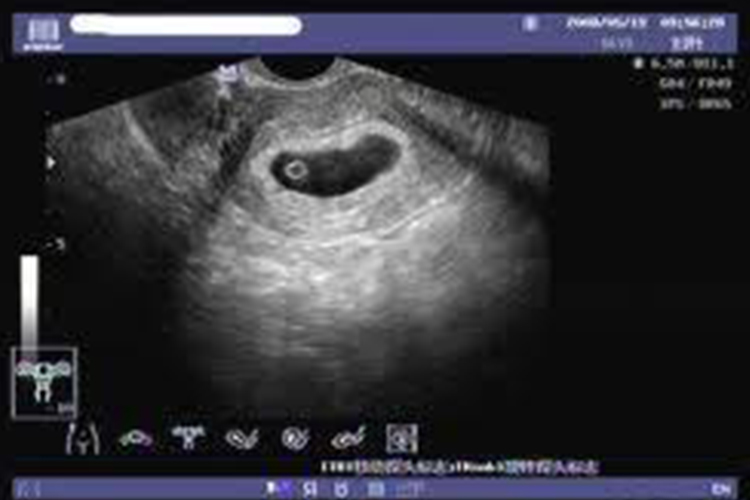

在超声检查报告中,27x17x27mm这样描述孕囊的大小,其中17mm通常代表孕囊的宽度,27mm分别代表孕囊的长度和高度。明确孕囊测量数值所代表的长宽高,对于评估胚胎发育和孕期保健具有重要的意义,有助于医生及时发现问题并采取相应的措施。

- 从孕囊的形态和发育特点,孕囊在早期多呈椭圆形或近似球形,长度和高度可能较为接近,27mm的两个数值分别代表了长度和高度。形态的描述有助于医生评估孕囊的发育情况,判断是否与孕周相符。

- 超声探头在检测孕囊时,会获取不同切面的图像,医生会选择能够清晰显示孕囊全貌的切面进行测量,并按照一定的标准和习惯记录数值。在这个过程中,测量的顺序和所代表的含义相对固定。